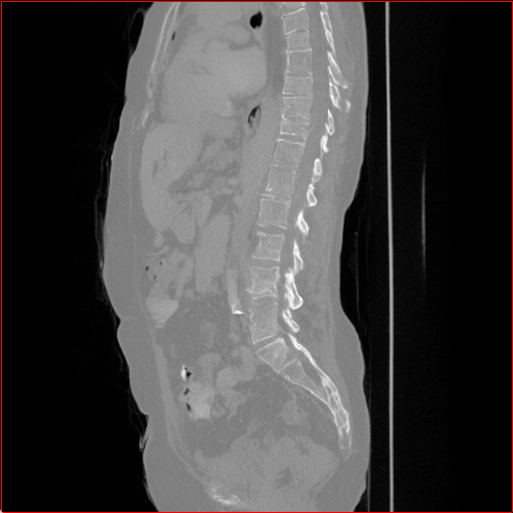

Figure 3 shows the generalizability of MAISI-v2 ControlNet for different body regions and voxel sizes. Figure 4 shows qualitative results for MAISI-v2 ControlNet on 5 types of tumors.

Figure 3: MAISI-v2 segmentation-guided results for small to large volume size and three different regions.

Head Region

1.1×1.1×1.11.1\times 1.1\times 1.1

mm

256×256×256256\times 256\times 256

Chest Region

1×1×11\times 1\times 1

384×384×384384\times 384\times 384

Abdomen Region

1×1×0.71\times 1\times 0.7

512×512×768512\times 512\times 768